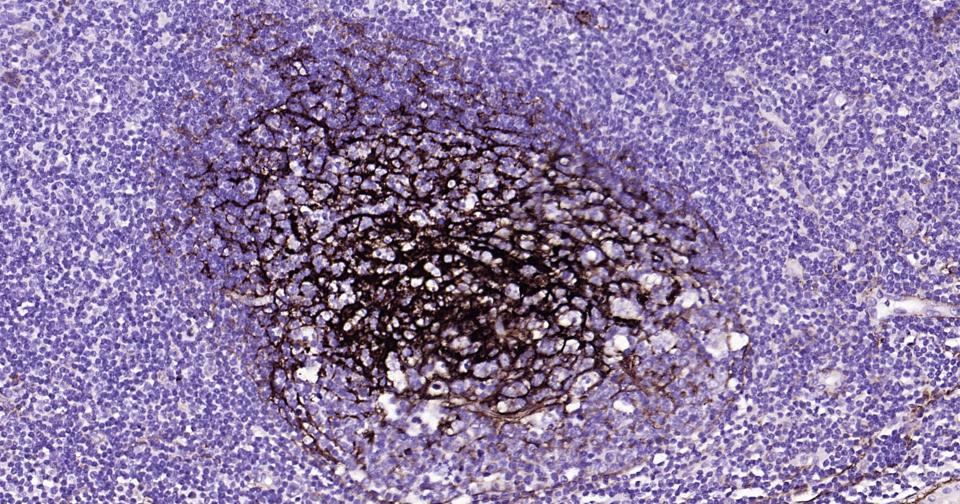

Paraformaldehyde-fixed, paraffin embedded Human Tonsil; Antigen retrieval by boiling in sodium citrate buffer (pH6.0) for 15 min; Antibody incubation with NGFR/p75NTR Monoclonal Antibody, Unconjugated(bsm-52253R) at 1:200 overnight at 4°C, followed by conjugation to the bs-0295G-HRP and DAB (C-0010) staining.